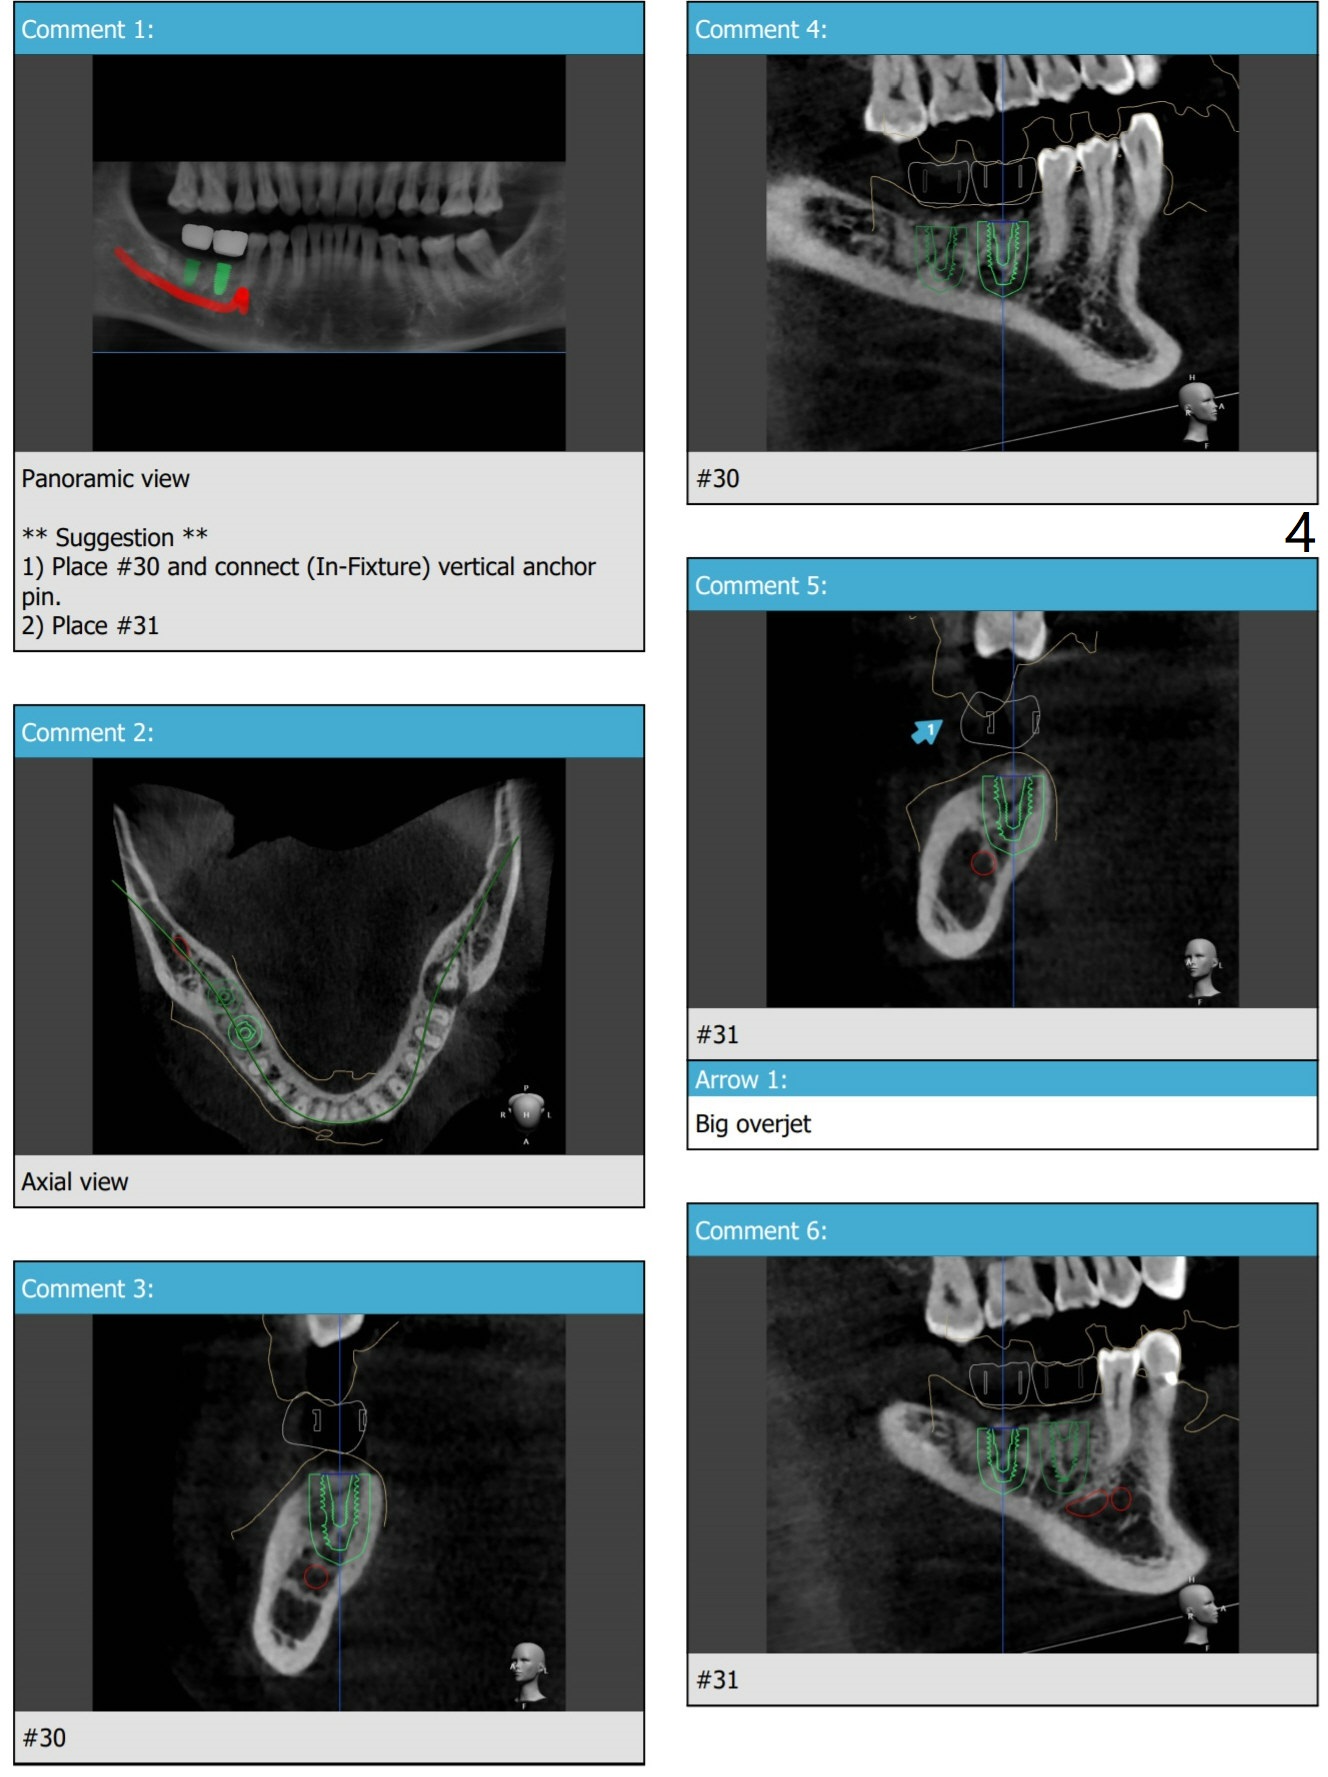

Lingual Access

Ridge top is flat with no deviation. If the keratinized gingiva is wide enough, no incision is required. If the patient uses water pik and torque is sufficient, place final abutments, fabricate provisional (preferably single units) and suture.